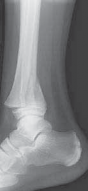

11. If there is any suspicion of an ankle injury, a complete plain radiographic ankle series should be performed. This consists of anteroposterior (AP), lateral, and mortise views (

FIG 2A–C

).

1. The mortise view is critical and is taken from anterior to posterior with the foot internally rotated 20 degrees to view

FIG 2•

Triplane fracture imaging. All ankle fractures require a plain radiographic series comprising AP (

A

), lateral (

B

), and mortise views (

C

D–G.

Three-dimensional CT reconstructions can aid in operative planning, especially for the difficult-to-

F G visualize intra-articular fractures.

the talus with a symmetric clear space seen medially and laterally.

1. The importance of the mortise view is seen in Tillaux fractures, where the anterior lateral fragment is often obscured by the overlap of the posterior fibula on the AP view and is not well visualized on the lateral view.

4. Computed tomography (CT) is required to fully understand many ankle fractures, and we often advocate three-dimensional postreduction CT scans (

FIG 2D–G

1. We advocate CT scans for intra-articular fractures that show any evidence of displacement on plain radiographs, and we routinely obtain three-dimensional CT scans for triplane and many Tillaux fractures after attempted closed reduction.

2. For any physeal fracture with apparent displacement in children with greater than 2 years of growth remaining, we advocate CT scanning of the ankle to evaluate for displacement, as we recommend operative treatment for trapped periosteum with greater than 2 mm of displacement.